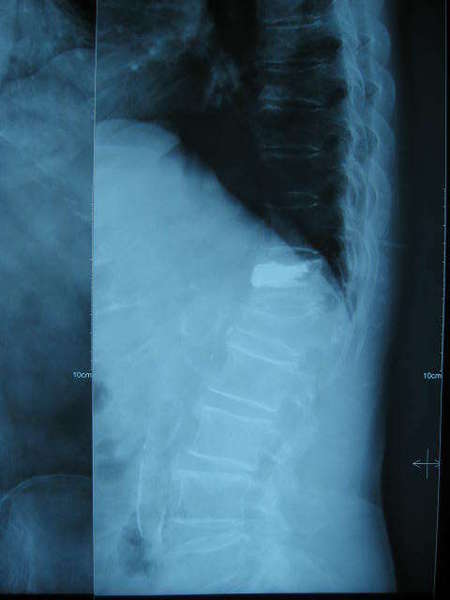

手术前X片---L1及T12均有压缩,且脊柱明显后凸畸形。

比较手术前后显示T12骨折椎体高度恢复,脊柱后凸畸形获得明显改善,填充骨水泥到位并均匀,无渗漏现象.